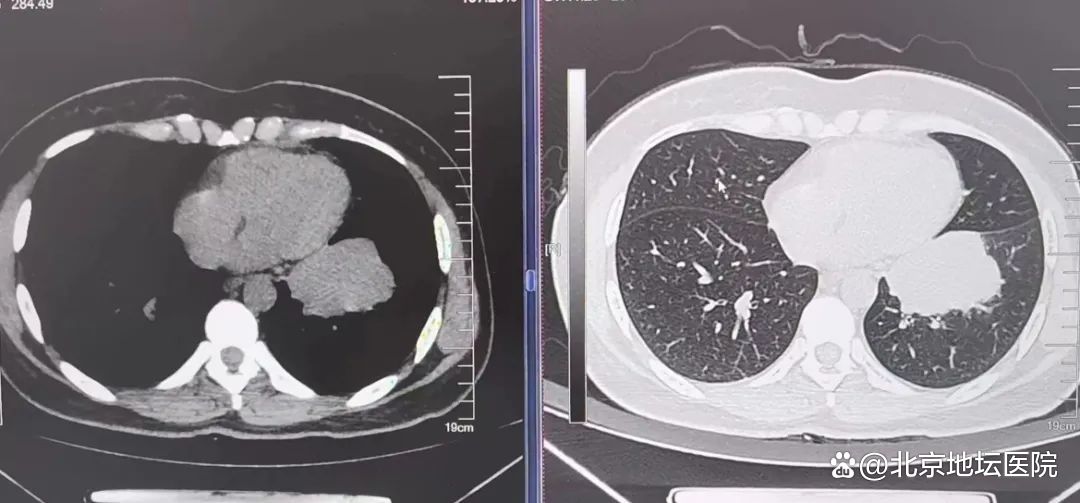

肺腺癌广泛胸膜转移,胸腔积液,治疗2年后病灶缩小(6次住院)